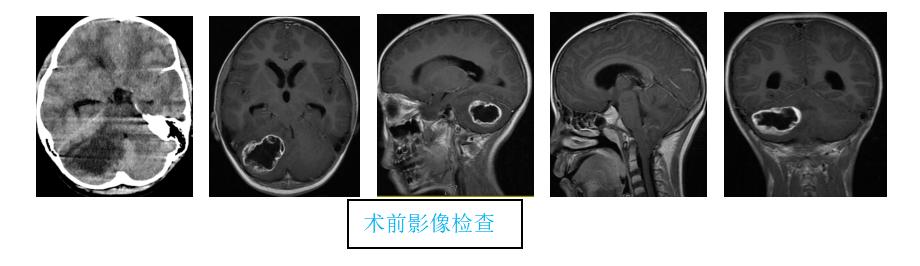

8月28日,拉萨市人民医院急诊科接诊了一名7岁藏族女性患儿。就诊时患儿神志已处嗜睡状态,在完善头部MRI检查后诊断患儿为小脑肿瘤合并小脑扁桃体下疝。

医生们在实地查看患儿病情并结合影像学表现后,判断患儿脑肿瘤周边脑组织水肿严重,极可能出现脑疝加重导致患儿呼吸功能障碍,需要尽快完善术前准备,尽早手术以防危及患儿生命。